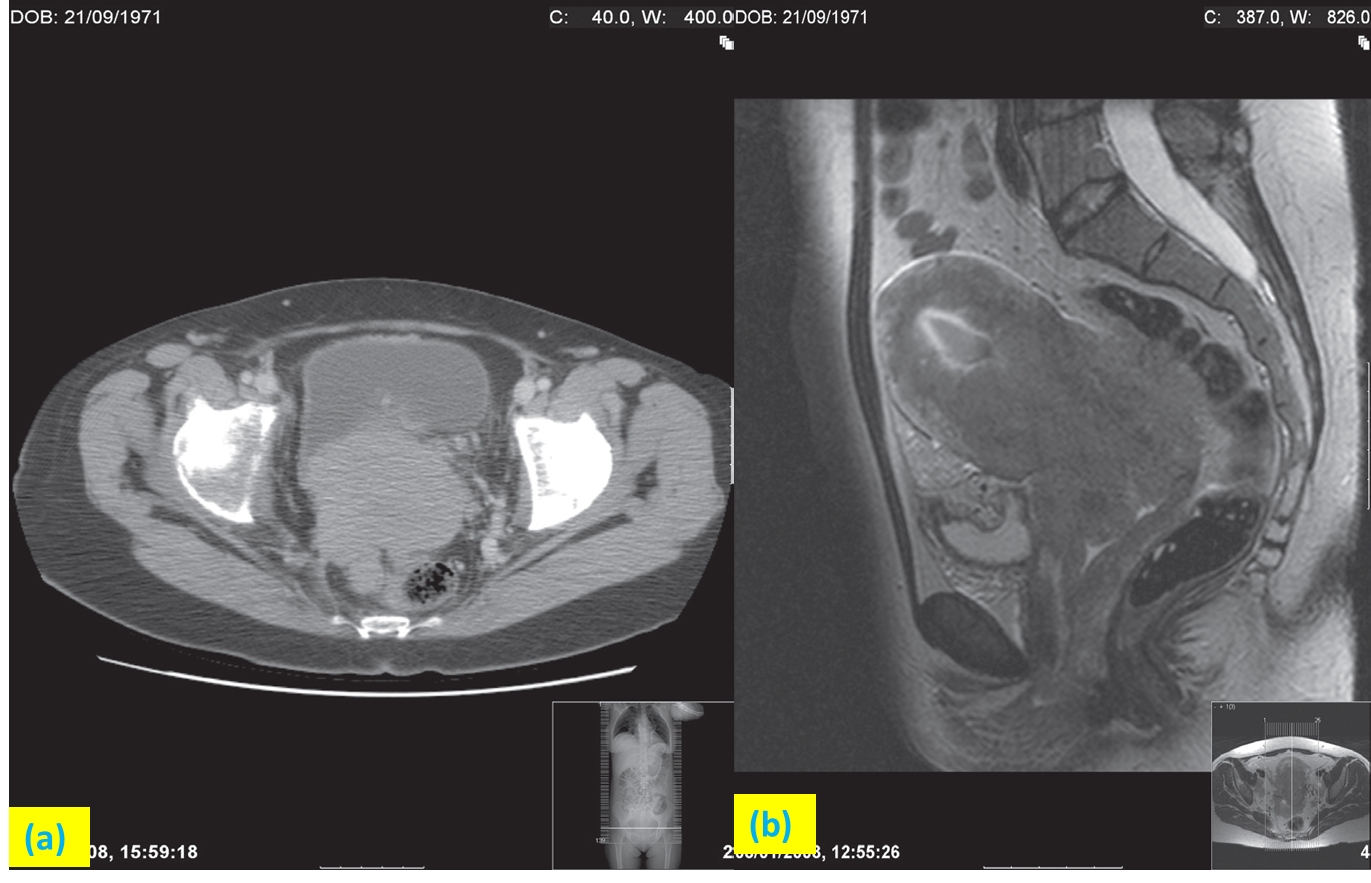

Advanced carcinoma of the cervix.

(a)CT scan showing a large tumour of the cervix extending into the rectum posteriorly.

(b) Sagittal T2-weighted MRI of the same patient. Note the tumour extending down the vagina.

Two different cases. T2 weighted sagittal MRI showing carcinoma of cervix